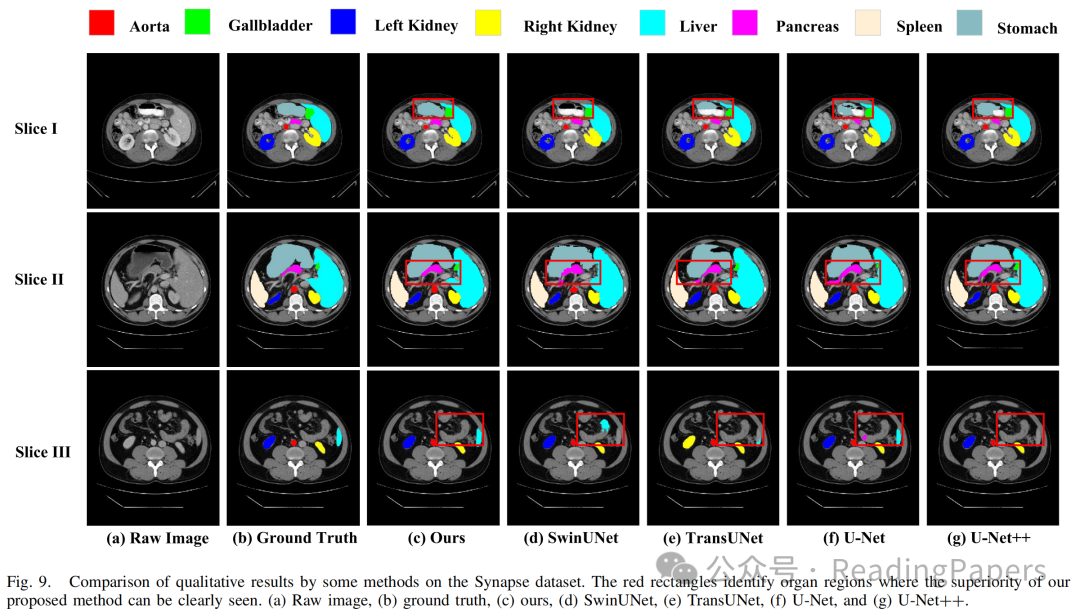

Transformer通过自注意力机制在医学图像处理中取得了显著进展,能够建模长距离语义依赖关系,但其缺乏卷积神经网络(CNN)捕捉局部空间细节的能力。本文提出了一种基于混合CNN-Transformer(MixFormer)特征提取骨干网络的新型分割网络,旨在提升医学图像分割的效果。MixFormer网络在下采样过程中无缝集成了Transformer和CNN架构的全局和局部信息。为了全面捕捉跨尺度的视角,作者引入了多尺度空间感知融合(MSAF)模块,有效实现了粗粒度与细粒度特征表示之间的交互。此外,作者还提出了混合多分支扩张注意力(MMDA)模块,用于在编码和解码阶段之间弥合语义差距,同时强调特定区域。最后,作者采用基于CNN的上采样方法来恢复低级特征,显著提高了分割精度。通过在多个主流医学图像数据集上的实验验证,MixFormer表现出卓越的性能。在Synapse数据集上,该方法达到了82.64%的平均Dice相似系数(DSC)和12.67 mm的平均Hausdorff距离(HD)。在自动心脏诊断挑战(ACDC)数据集上,DSC达到了91.01%。在国际皮肤成像协作(ISIC)2018数据集上,模型的平均交并比(mIoU)为0.841,准确率为0.958,精确率为0.910,召回率为0.934,F1得分为0.913。在Kvasir-SEG数据集上,平均Dice为0.9247,mIoU为0.8615,精确率为0.9181,召回率为0.9463。在CVC-ClinicDB数据集上,平均Dice为0.9441,mIoU为0.8922,精确率为0.9437,召回率为0.9458。这些结果表明,MixFormer在分割性能上优于大多数主流分割网络,如CNN和其他基于Transformer的结构。

IV. 实验